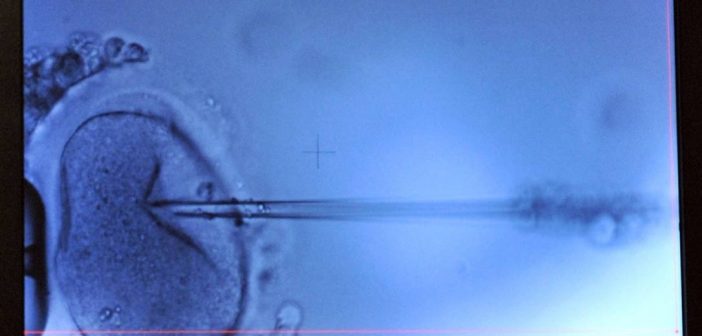

Os especialistas transferiram o DNA materno para o óvulo de uma doadora, por meio de uma técnica conhecida como transferência do fuso maternal (MST, na sigla em inglês), e depois o fecundaram com o espermatozoide do pai.

Para evitar que defeitos nessa organela celular sejam passados aos filhos, usa-se apenas o núcleo do óvulo da mãe — onde está a maior parte do material genético —, que é inserido num óvulo doado cujo núcleo foi removido.

Como uma pequena quantidade de DNA da doadora permanece na mitocôndria do óvulo, a criança gerada nasce com material das duas mulheres e com o do pai, que vem por meio do espermatozoide.